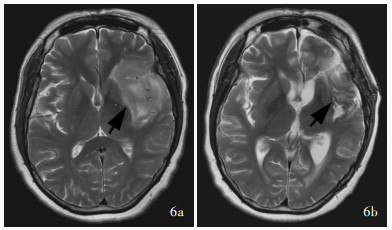

Sun GC , Shu XJ , Zheng XQ , Ma XD , Cheng G , Liu JL , Chen L , Zhang JN . The transfrontal isthmus approach for insular glioma surgery. J Neurosurg, 2022, 139: 20- 28.

|